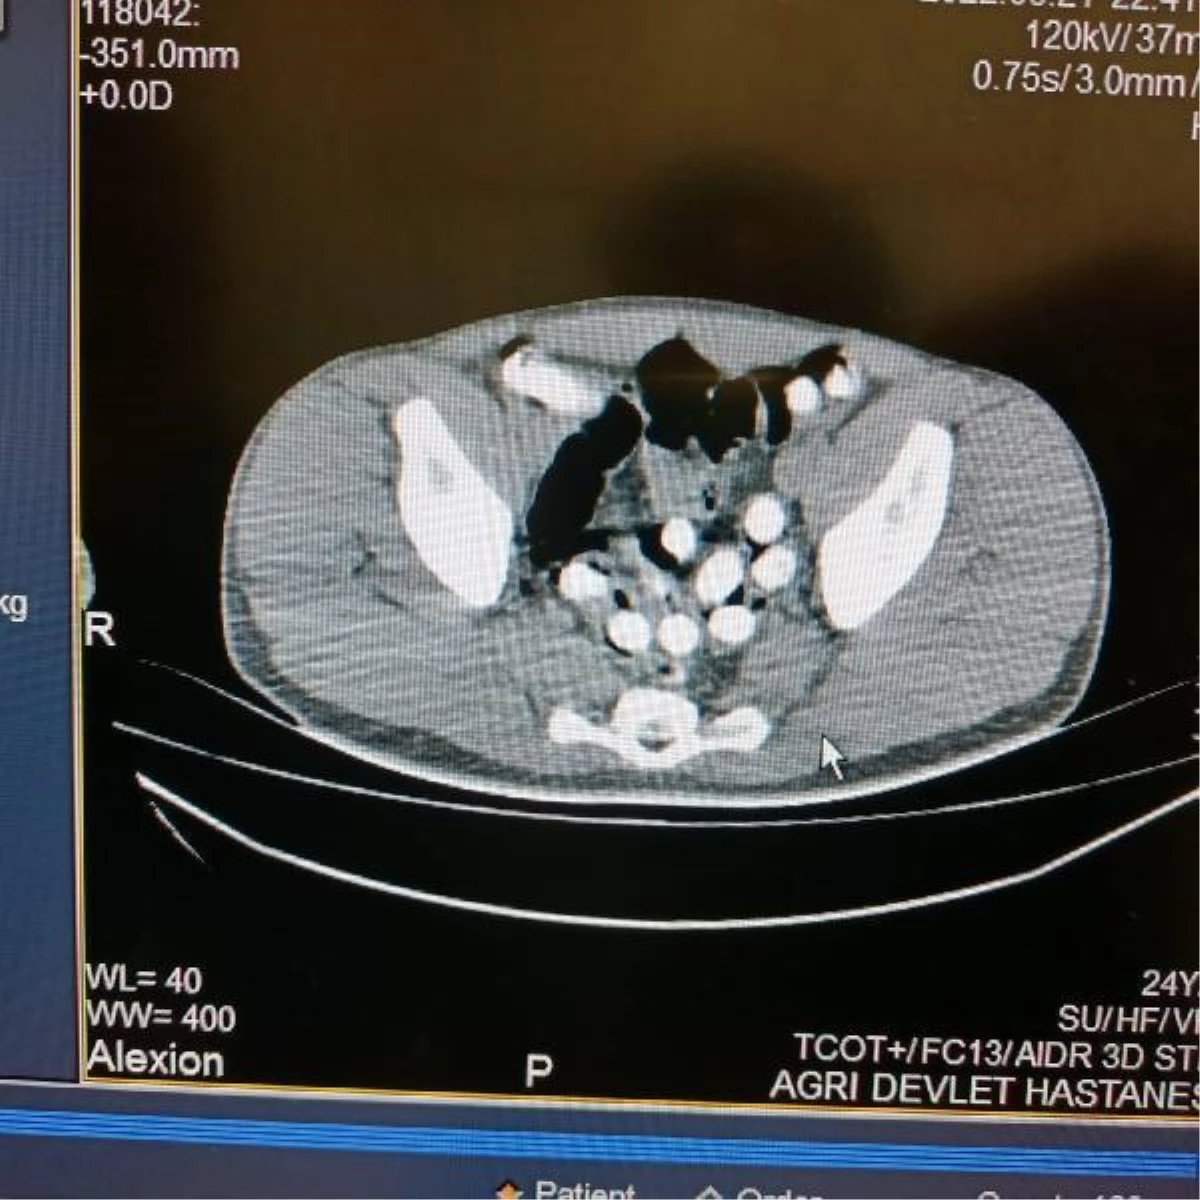

İl Emniyet Müdürlüğü Narkotik Suçlurla Mücadele Şube Müdürlüğü ekipleri, uygulama noktasında durdurulan otobüste yolculuk eden İranlı M.H.'nin üzerini aradı. Polisin midesindeki şişlikten şüphelendiği M.H., 6 kapsül halinde 62,35 gram afyon sakızını kustu. Hastaneye götürülen M.H.'nin çekilen röntgeninde mide ve bağırsak kısmında başka kapsüller bulunduğu da görüldü. Ek gözaltı süresi alınan şüpheli, doğal yollarla mide ve bağırsağındaki afyon sakızlarını çıkardı. Midesinden 102 kapsül halinde 1 kilo 126 gram afyon sakızı çıkarılan şüpheli, sevk edildiği adliyede çıkarıldığı hakimlikçe tutuklandı.